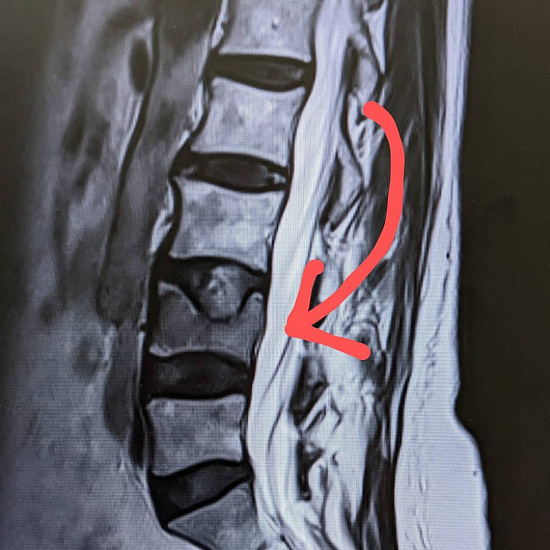

При магнитно-резонансной томографии был выявлен перелом четвертого поясничного позвонка на фоне мягкотканого образования в теле позвонка, вследствие чего пациентке было предложено выполнить дообследование в виде компьютерной томографии.

По результатам КТ и МРТ было заподозрено наличие агрессивной гемангиомы или плазмоцитомы позвонка как причины перелома.